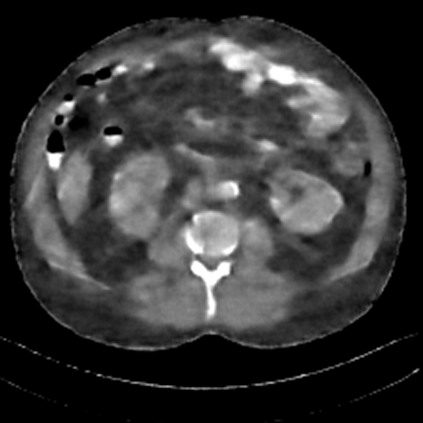

Sparse-view computed tomography (CT) -- using a small number of projections for tomographic reconstruction -- enables much lower radiation dose to patients and accelerated data acquisition. The reconstructed images, however, suffer from strong artifacts, greatly limiting their diagnostic value. Current trends for sparse-view CT turn to the raw data for better information recovery. The resultant dual-domain methods, nonetheless, suffer from secondary artifacts, especially in ultra-sparse view scenarios, and their generalization to other scanners/protocols is greatly limited. A crucial question arises: have the image post-processing methods reached the limit? Our answer is not yet. In this paper, we stick to image post-processing methods due to great flexibility and propose global representation (GloRe) distillation framework for sparse-view CT, termed GloReDi. First, we propose to learn GloRe with Fourier convolution, so each element in GloRe has an image-wide receptive field. Second, unlike methods that only use the full-view images for supervision, we propose to distill GloRe from intermediate-view reconstructed images that are readily available but not explored in previous literature. The success of GloRe distillation is attributed to two key components: representation directional distillation to align the GloRe directions, and band-pass-specific contrastive distillation to gain clinically important details. Extensive experiments demonstrate the superiority of the proposed GloReDi over the state-of-the-art methods, including dual-domain ones. The source code is available at https://github.com/longzilicart/GloReDi.